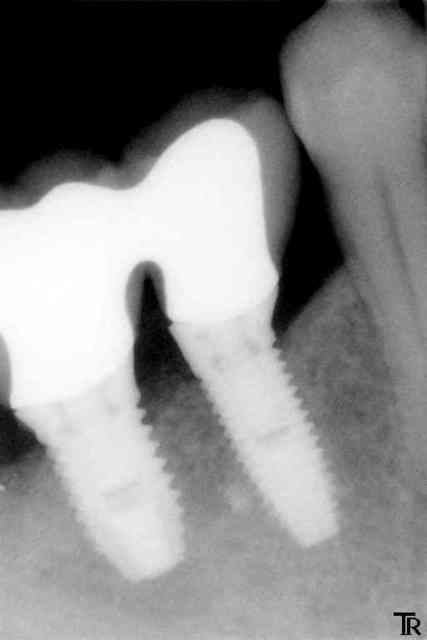

Allez un cas un petit peu limite

pilier Ti procera à fond et couronnes avec un léger défaut d'ajustage ou pas vraiment à fond ?

C'est vrai que la gencive à parfois tendance à venir interférer au scellement en venant se clipser autour du pilier au dessus des limites car mon labo ne veux pas faire des limites juxta

Et il reste un peu de ciment en sous gingivale.

A un mois, je n'ai noté aucune inflammation gingivale.

Et vous vous faite quoi ici ?

ici tu ne risques pas grand choses l'espace biologique étant présent entre le bord osseux et tes limites de coiffes.

en revanche le souci c'est le premier implant qui est trop éloigné de la prémolaire (sans la solidarisation avec les suivants il y aurait déjà sûrement une cratérisation par stress mécanique)

tu as implanté quand?